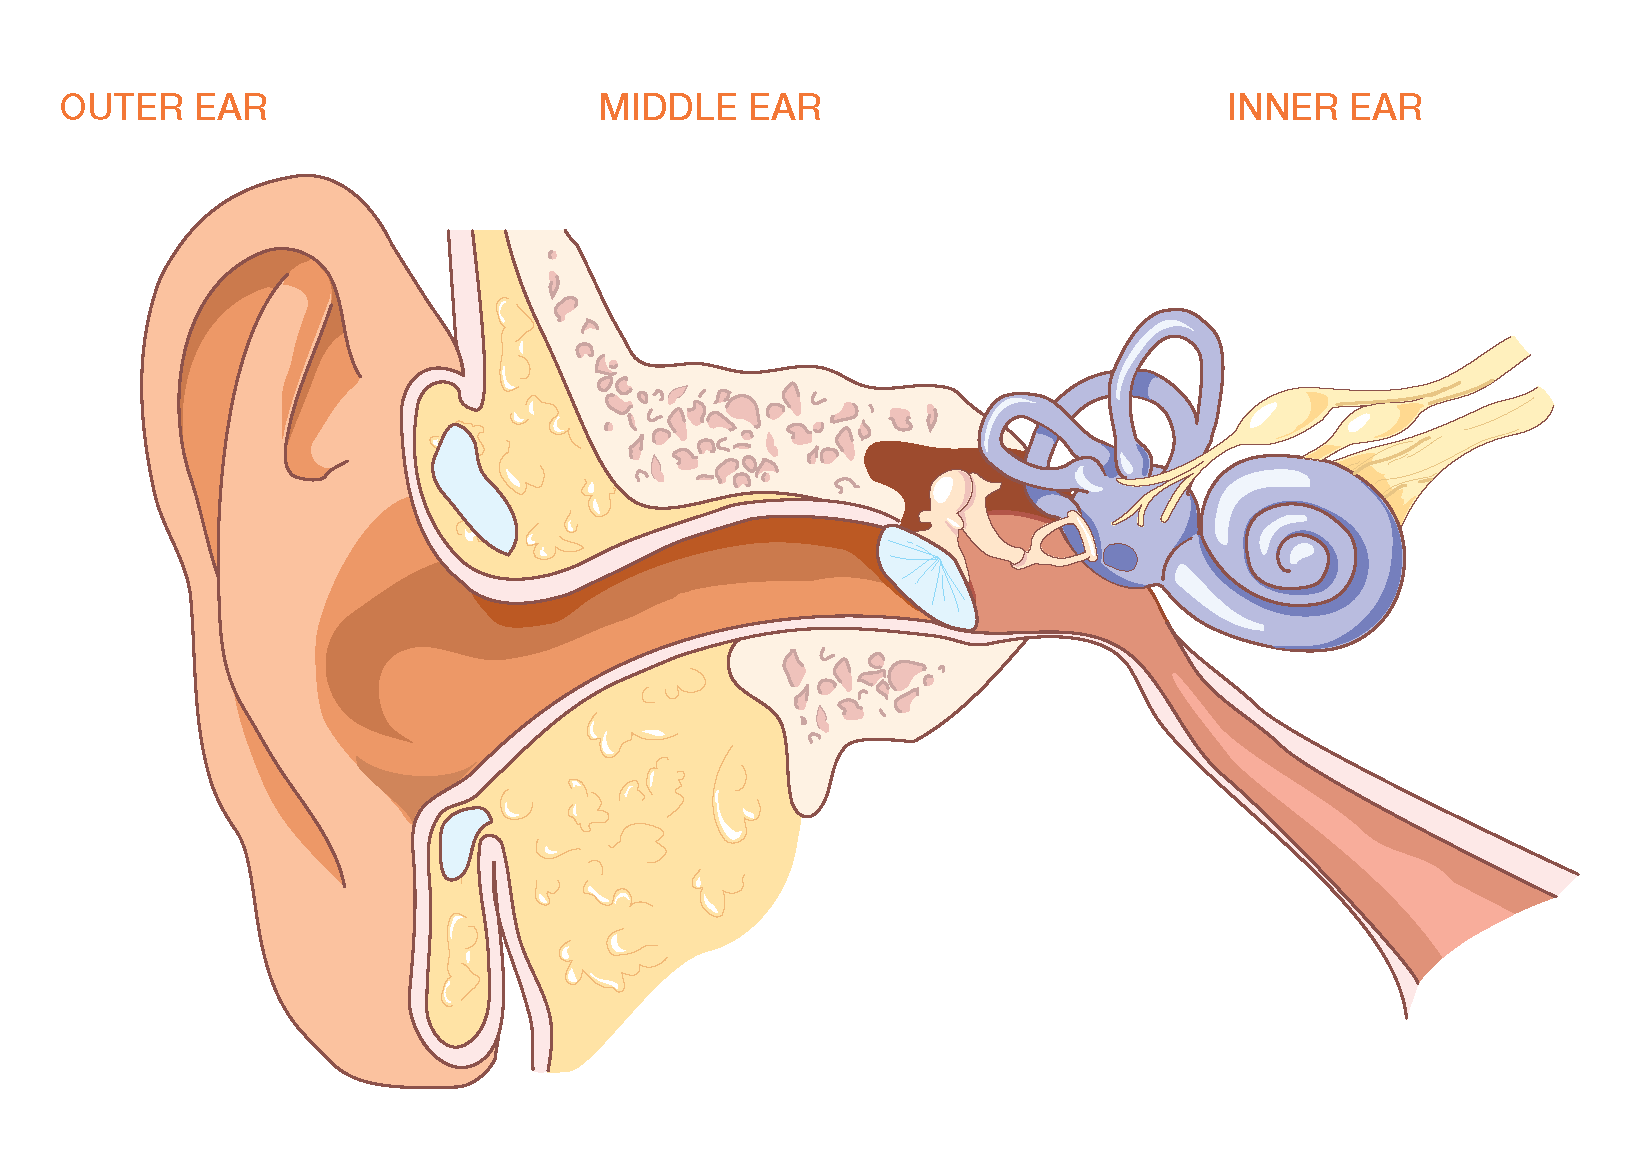

Case Report

J Otol Rhinol 2013, 2:4

10.4172/2324-8785.1000132